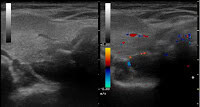

Während gesunde Nebenschilddrüsen aufgrund ihres gleichen Schallmusters wie die Schilddrüse normalerweise sonographisch nicht abzugrenzen sind, können die immer gutartigen Nebenschilddrüsenadenome per Ultraschall häufig erkannt werden.